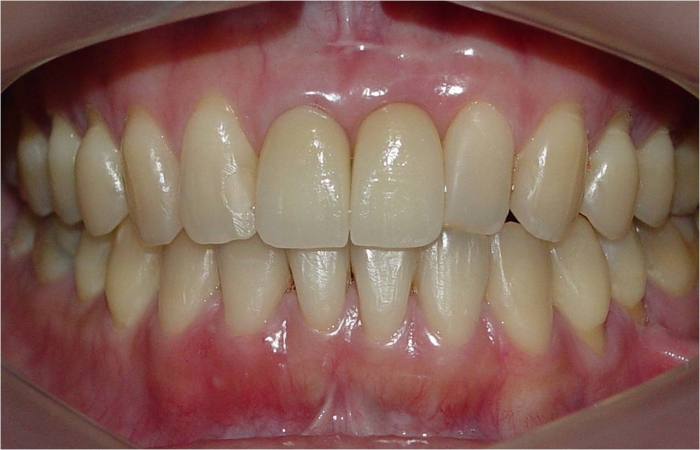

Imagens iniciais com elemento 21 comprometido